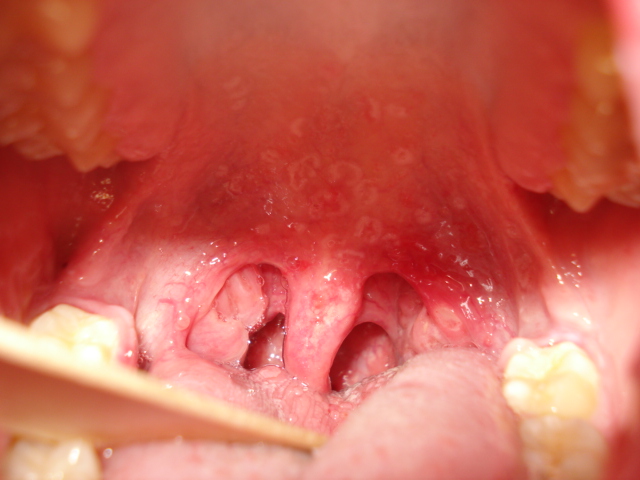

Dolor de garganta. Diez días de evolución.

Posibles respuestas a Foto 1: AFTAS. otras posibles pero menos ...virus, cándidiasis...